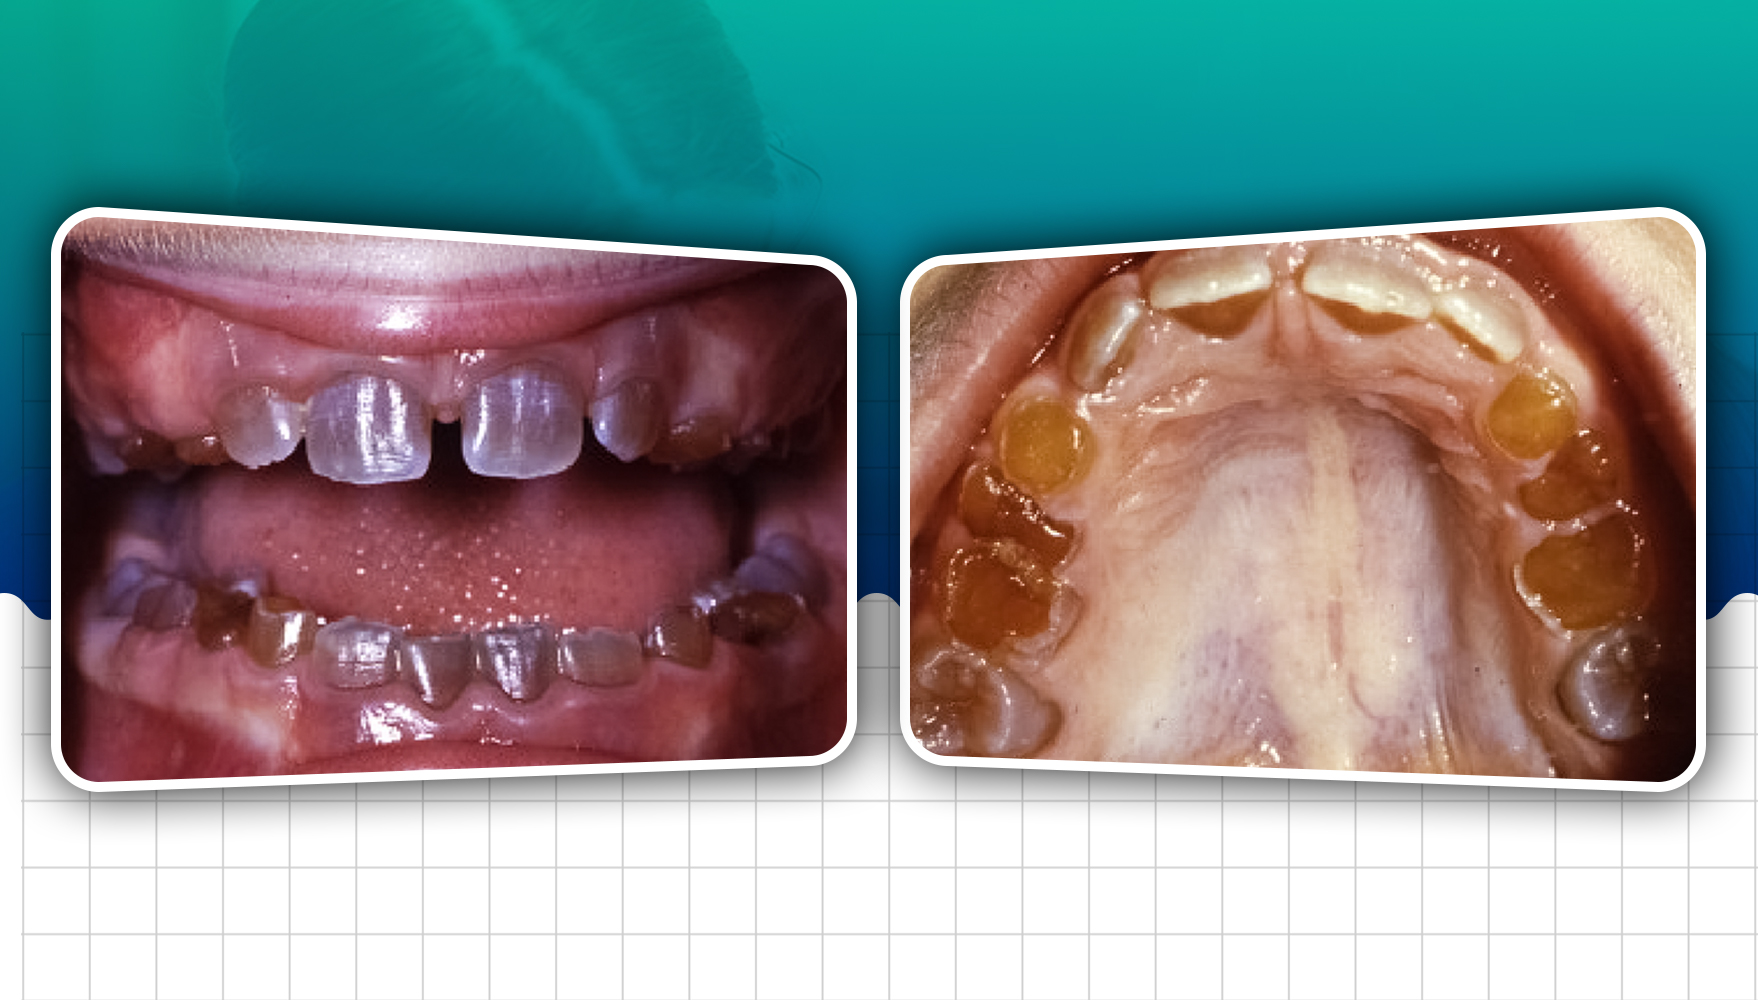

Dentinogenesis imperfecta is an autosomal dominant condition affecting both deciduous and permanent teeth. Affected teeth are grey to yellowish brown and have broad crowns with constriction of the cervical area, resulting in a tulip shape.

- The teeth are blue-grey or amber-brown and opalescent.

- The crowns of the deciduous and permanent teeth wear rapidly after the eruption, and multiple pulp exposures may occur.

- The dentin is amber and smooth.